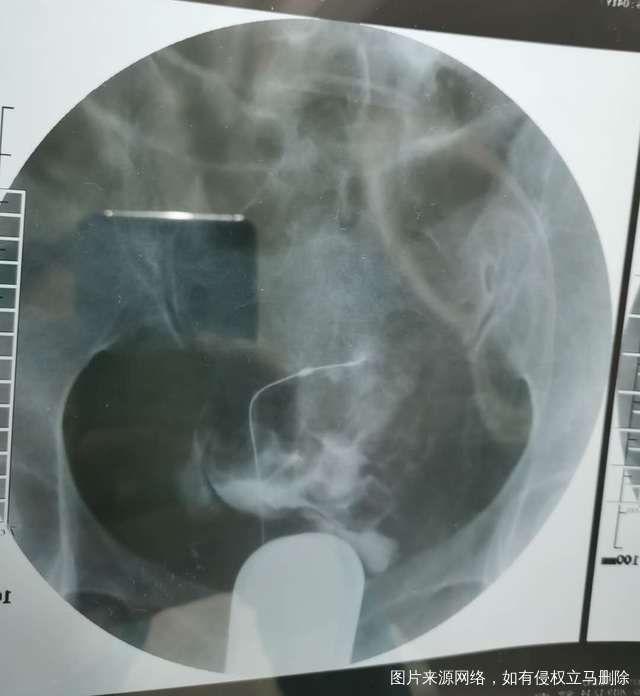

我这个是做了输卵管介入手术,请问输卵管是通了